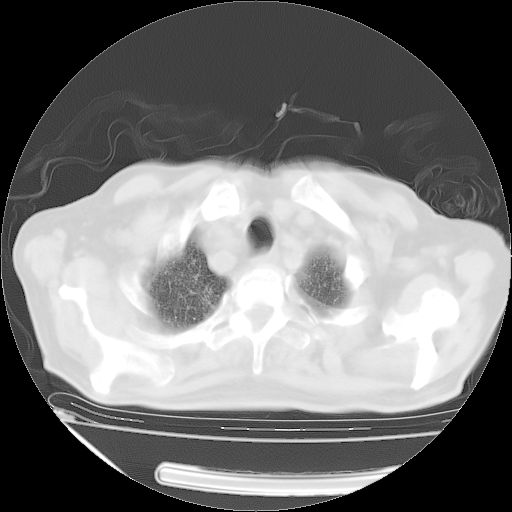

经过24天治疗,岳父的病情基本稳定。生活基本可以自理,可以下床活动。呼吸困难早已消失。体温基本正常。

只是甲强龙用80mg时血小板升到正常,改为60mg后又降到63×10*9/L。

主要治疗甲强龙80mg×14天,60mg×10天;同时抗结核(异烟肼+利福平+乙胺丁醇)。环磷酰胺0.1 tid 10天。

特别感谢胡教授、高管、桃子版主给出关键的治疗建议。桃版把所有肺部影像和全部临床资料请所在医院呼吸科、感染病科、结核科、临床免疫科专家会诊。临床免疫科专家制定了完整的治疗方案。